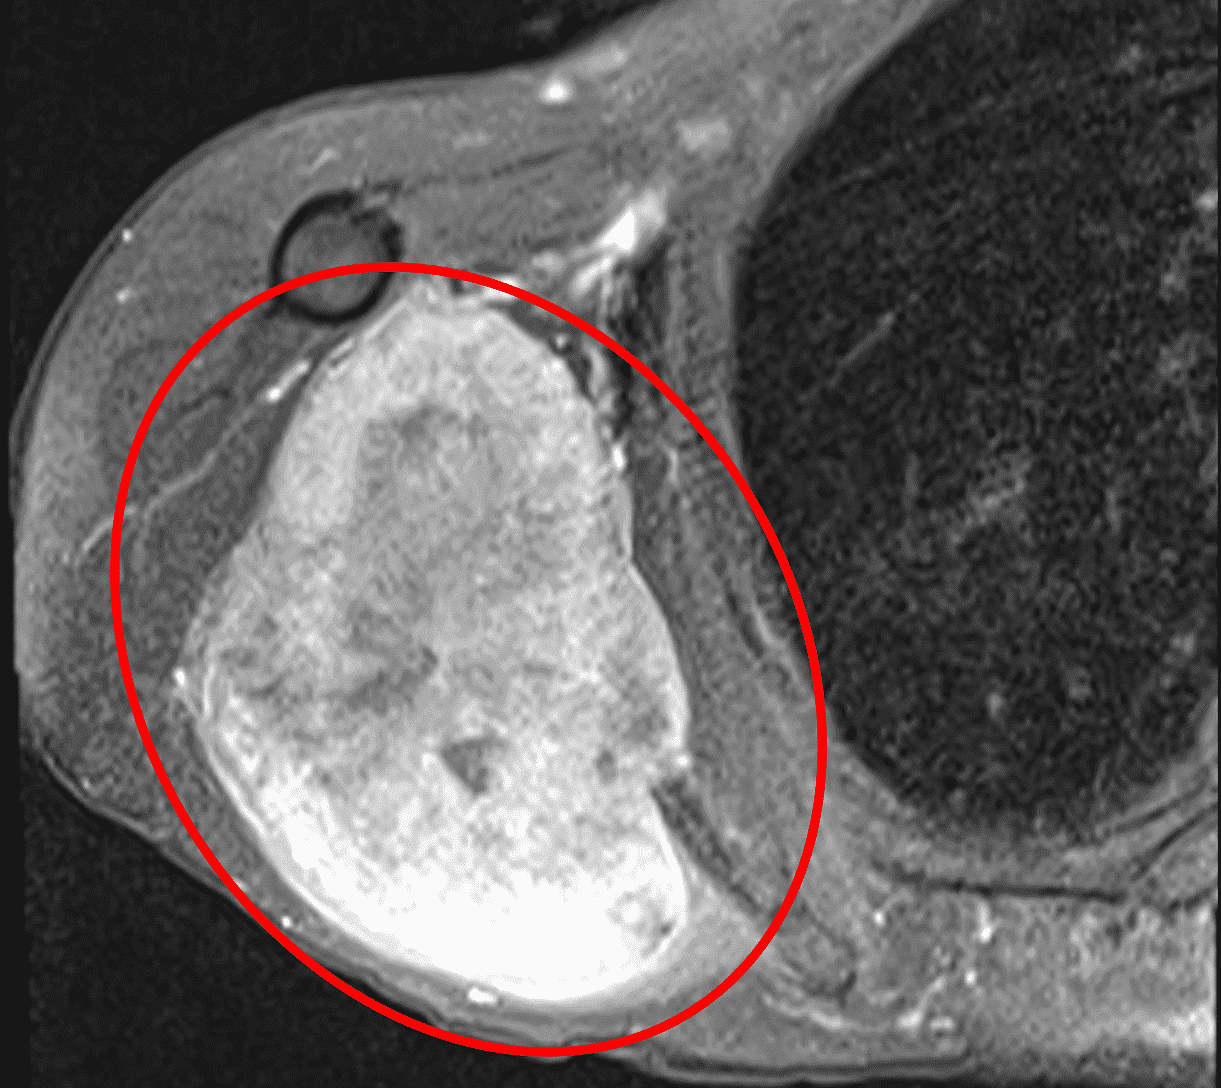

Для злоякісних утворень оптимальнішими є контрастні фази (зобр. 2). Фази STIR допомагають продемонструвати ступінь перитуморального набряку. Якщо МРТ недоступна, комп’ютерна томографія (КТ) є наступним найбільш інформативним методом візуалізації, що забезпечує детальні крос-секційні зображення, які можуть допомогти визначити розмір і ступінь ураження, про яке йдеться. Ураження лімфатичних вузлів не є поширеним при ETSTS, але патологічна лімфаденопатія, виявлена під час фізикального обстеження або виявлена на візуалізації, якщо вона є, повинна спонукати до поглиблення діагностичного пошуку.

Зобр. 2: На МРТ показана веретеноклітинна саркома високої ступеня злоякісності у задній ділянці правого плеча. А) Т1 фаза показує злоякісну пухлину, яка ізоінтенсивна до м’язової тканини.

Figure 2: (B) Постконтрастна фаза показує гіперінтенсивну пухлину.